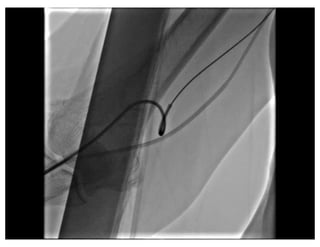

Balloon Assisted Tracking

Patel T, et al CCI 2012

Razor Effect

Razor Effect Balloon AssistedTracking Patel T, et al CCI 2012